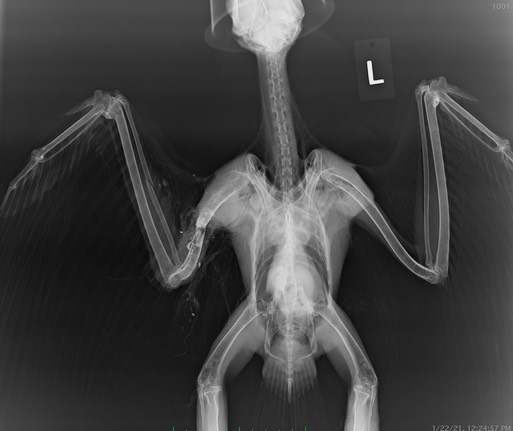

Red-tailed Hawk 21-010

21-010 was hit by a car near Prosser, WA. The collision dislocated his right coracoid. But that was just the beginning. The hawk had a healed fracture in his right clavicle.

His lower beak had been broken and was very overgrown as a result. His beak was coped while he was under anesthesia. It will likely take several more copings before it begins to look normal.

And finally, the hawk had a crooked toe on his left foot that was the result of a gunshot injury. He had been shot some months ago and recovered. Even with a horribly overgrown beak and a mostly nonfunctional left halux (the grabber toe) the hawk was in good body condition. All this before his first birthday.